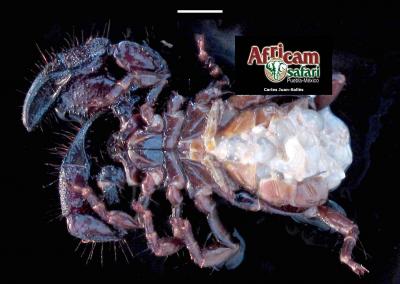

El examen post mortem ofrece una oportunidad única de acceso a todos los tejidos del paciente para diagnóstico de las causas de enfermedad y muerte, y por lo tanto es esencial para medicina preventiva y curativa en grupos de animales, seguimiento de casos, estudios sobre enfermedades, control de zoonosis, medicina de la conservación, y patología forense. En Noah's Path pensamos que un examen post mortem de este tipo de fauna debería ser realizado siempre que sea posible por patólogas/os especializadas/os con el fin de obtener el máximo de información y obtener las muestras más adecuadas.